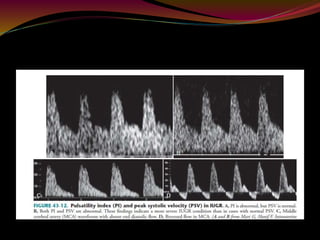

 Systolic-to-diastolic (S/D) ratio = Peak systolic

velocity/End diastolic velocity (PSV/EDV)

 Resistive index (RI) = (PSV − EDV)/PSV

 Pulsatility index (PI) = (PSV − EDV)/Mean velocity

Waveform

 “Saw tooth" pattern with flow always in the forward

direction.

 An abnormal waveform shows absent or reversed

diastolic flow.

SEVERITY

 In growth-retarded fetuses and fetuses developing

intrauterine distress, the umbilical artery blood

velocity waveform usually changes in a progressive

manner as below

 reduction in end diastolic flow: increasing RI values,

PI values and S/D ratio

 absent end diastolic flow (AEDF): RI = 1

 reversal of end diastolic flow (REDF)